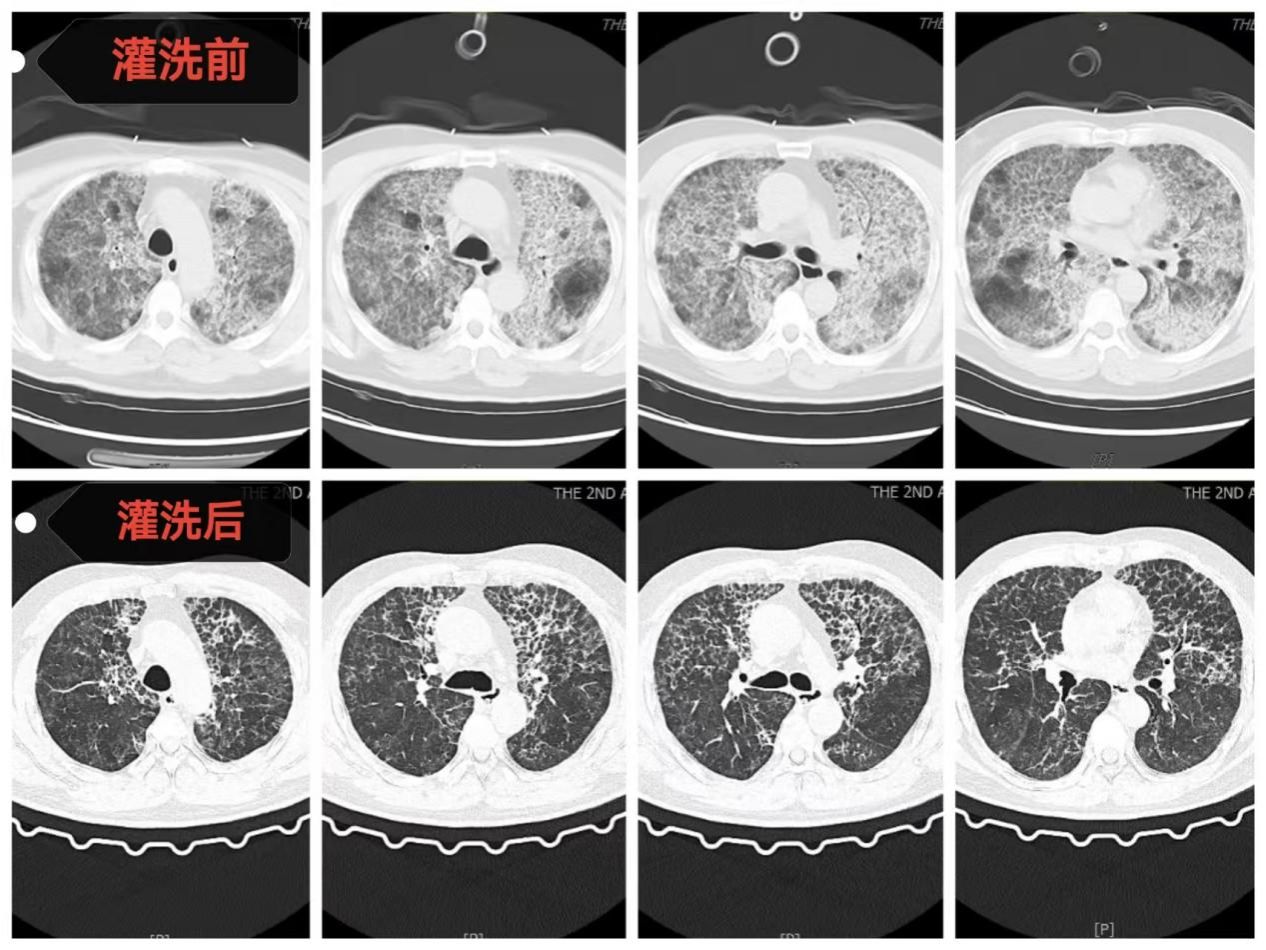

方萍主任医师团队与患者家属进行充分沟通并取得支持后,一场多学科协作的生命保卫战打响。首先,麻醉科雷晓鸣主任医师和宋正川副主任医师团队为患者实施全麻下双腔气管插管有创呼吸支持,随后呼吸与危重症医学科和急诊科ECMO团队(呼吸与危重症医学科方萍主任医师、邓文静主治医师、樊娜主治医师、刘勇护士、韩青青护士以及急诊科冯辉主治医师等)立即为患者建立VV-ECMO通路并顺利转机,患者氧合情况迅速稳定。随后,手术台上,方萍主任医师、黎蒙护士以及手术室多名医护人员紧密配合,共使用20000毫升37℃生理盐水为患者进行双肺“深度清洁”。灌洗回收液从最初的浑浊“牛奶状”逐渐变得清澈,回收率>90%,快速直观地展现了灌洗的效果。

术后,患者在ECMO支持下转入呼吸与危重症医学科RICU继续治疗。在长达11天的ECMO支持期间,RICU医护团队日夜坚守,严密监测,精准调整抗感染、抗凝策略和ECMO、呼吸机支持参数。随着患者自身肺功能逐渐改善,复查血气指标显著好转,胸部CT显示双肺弥漫性阴影较入院时明显吸收。最终成功撤除ECMO,并顺利脱离呼吸机、拔除气管插管。出院时,患者在不吸氧的情况下,血氧饱和度维持在正常水平,活动能力恢复,实现了从“命悬一线”到“行动自如”的生命奇迹。

全肺灌洗前后影像资料对比